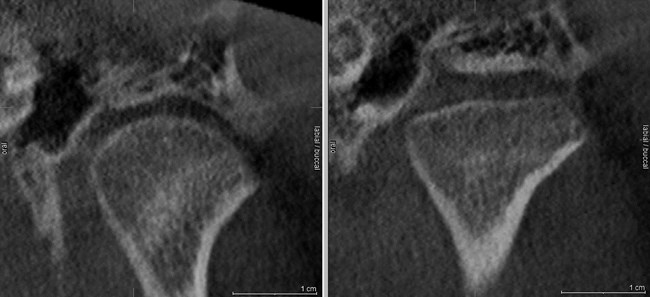

W celu oceny położenia głów żuchwy w ssż oraz wykluczenia zmian morfologicznych narządu żucia wykonano badanie tomografii stożkowej CBCT o dużym polu obrazowania, w zwarciu nawykowym. W badaniu stwierdzono asymetrię ustawienia głów żuchwy w panewkach – prawa głowa żuchwy była ustawiona bardziej dotylnie niż lewa. Z kolei lewa głowa żuchwy była ustawiona centralnie w panewce w płaszczyźnie przednio-tylnej, ale wysunięta do dołu w porównaniu z prawą głową żuchwy (ryc. 1). Na przekrojach czołowych prawa głowa żuchwy miała kształt wypukły, a lewa była spłaszczona, co może wskazywać na zmiany zwyrodnieniowe (ryc. 2). W badaniu CBCT nie stwierdzono obecności zmian zapalnych okołowierzchołkowych, które mogłyby być przyczyną dolegliwości bólowych, jak też zmian zapalnych zatok obocznych nosa.

Ryc. 1. Przekroje strzałkowe ssż w tomografii stożkowej ukazują asymetrię ustawienia głów żuchwy w panewkach – prawa głowa żuchwy ustawiona bardziej dotylnie niż lewa. Lewa głowa żuchwy jest ustawiona centralnie w panewce w płaszczyźnie przednio-tylnej, ale wysunięta do dołu w porównaniu z prawą głową żuchwy.